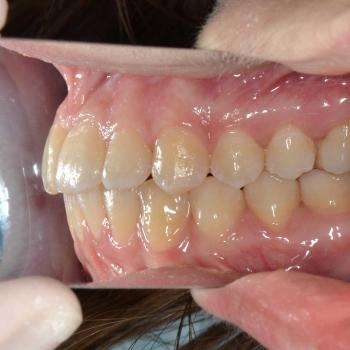

Eszter és édesanyja az iskolai fogorvosuk javaslatára kerestek fel, mert a kolléga, az esztétikai problémát okozó torlódás mellett, Angle II. osztályú funkciós eltérést is tapasztalt. Szerencsére ezeken felül egyéb eltérésre a konzultáció alkalmával sem derült fény.

Eszter a kezelés megkezdésekor headgear típusú fogszabályozó készüléket kapott annak érdekében, hogy a felső nagyőrlőket hátrafelé mozgassuk, illetve, hogy a keletkező rést felhasználjuk a kisőrlők és a szemfogak hátramozdítására is. Az így felszabadult hely az Eszter által választott hagyományos fém fogszabályozó segítségével felhasználható volt a metszőfogak elrendezéséhez, azok túlzott előredőlése nélkül.

A kezelés eredményeként minden kiindulási problémát sikerült megoldani és egy esztétikailag és funkcionálisan is szép mosolyt létrehoznunk.